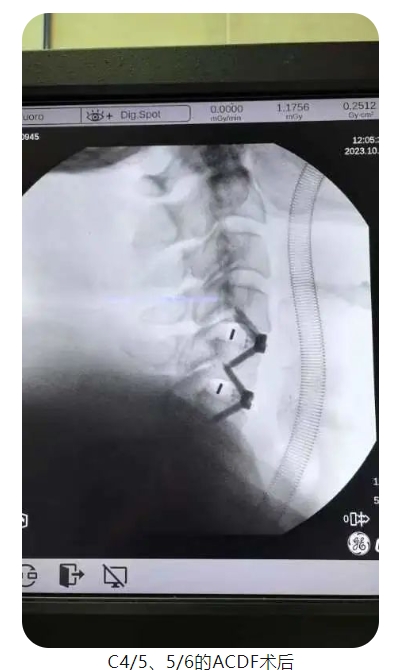

考慮到李叔年紀(jì)較大且有尿毒癥等多種基礎(chǔ)病,為了讓患者獲得更好的治療效果,確保手術(shù)方案更加科學(xué)、精細(xì),王清富帶領(lǐng)骨科中心團(tuán)隊(duì)進(jìn)行了充分論證及術(shù)前準(zhǔn)備,在與患者及家屬充分溝通后,歷時(shí)一個(gè)半小時(shí),順利為李叔行前路頸椎間盤切除椎間植骨融合內(nèi)固定術(shù)(ACDF),成功摘除突出椎間盤、椎管減壓及植骨融合,術(shù)后患者頸部?jī)H有一約3cm大小的切口。術(shù)后當(dāng)天,患者頸肩部困痛伴左上肢疼痛麻木不適癥狀消失,四肢肌力較前逐步好轉(zhuǎn),癱瘓癥狀較前明顯改善。次日,李叔就能下地正常行走。